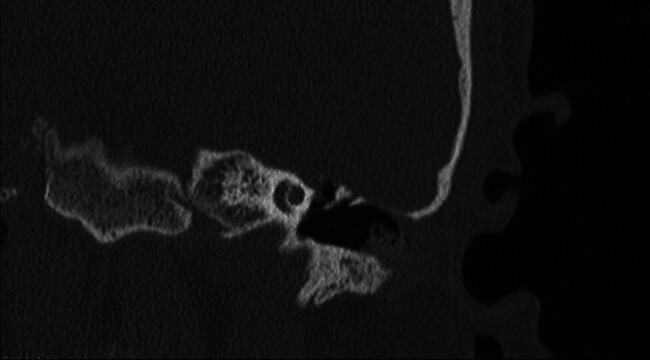

Objective: Occasionally, repair of tegmen defects can be complicated by the ossicular chain protruding above the floor of the middle fossa, which traditionally requires disarticulation and reconstruction of the ossicles to manage. This manuscript describes modifications of previously described techniques to address this surgical problem.

Participants: In this case series we present three patients with tegmen defect and encephalocele where the ossicles protruded over the floor of the middle fossa. In one instance, a "manhole cover" was created by concentrically layering hydroxyapatite cement around the tegmen defect and placing a piece of calvarium harvested from the bone flap over the defect. In another case, a "bony igloo" was drilled into harvested bone flap and placed over the defect, effectively creating a neo-epitympanum.

Conclusions: The "manhole cover" and "bony igloo" techniques are pragmatic solutions to this rare but complex surgical problem.